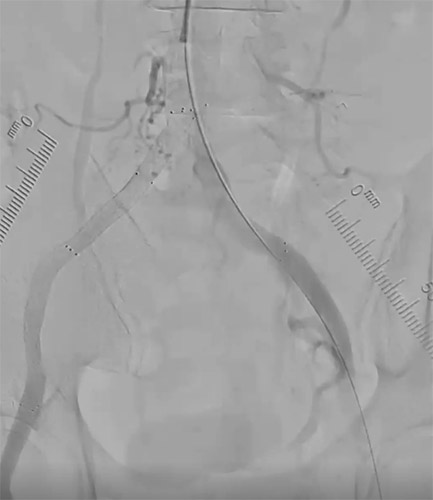

SFAの最終造影を行い、圧較差も無くなり良好な血流を確認し治療終了。【図12・図13】